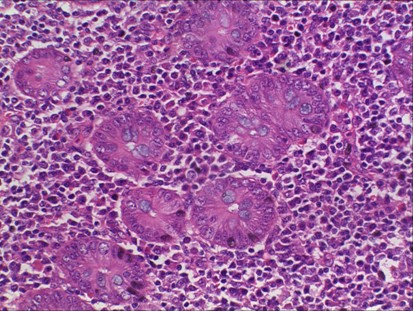

下面是實(shí)拍的一些圖片: